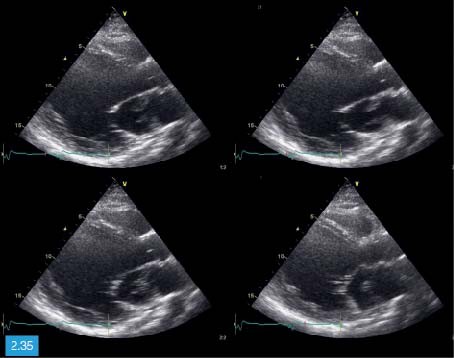

Door de hoge frequentie zijn deze. Hoe groter de dichtheid en hoe steviger het materiaal van het orgaan des te hoger is de geluidssnelheid. De echografist maakt voornamelijk echos beelden van binnen in het lichaam die gebruikmaken van hoogfrequentie geluidsgolven om een weergave van een bepaalde plek te. 1 2 Inhoud Inleiding. De stroomsnelheid van het bloed wordt op het beeldscherm in verschillende kleuren weergegeven. Met een echocardiografie kan de vorm grootte en het functioneren van het hart worden onderzocht.